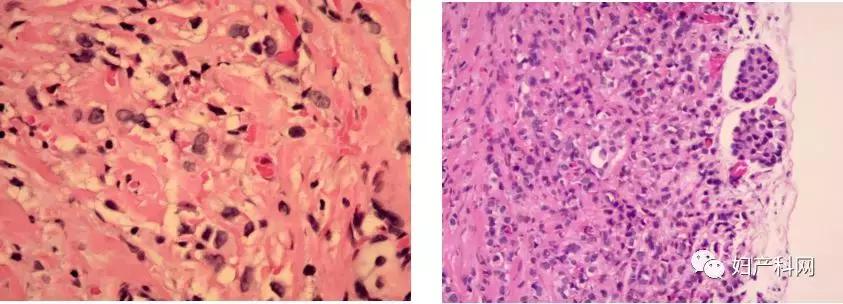

术后常规病理报告提示(见图4):(双侧)卵巢、输卵管、卵巢血管区转移性癌,符合转移性乳腺癌所见。(腹腔积液)涂片内找见癌细胞。子宫浆膜表面见转移性癌,符合转移性卵巢癌所见。

结合患者术中及术后病理结果,术后转移性卵巢癌诊断明确。

卵巢作为一个可以生长多种肿瘤的器官,曾一度被认为发生在卵巢上的转移瘤比较罕见。然而大量资料的统计,逐渐发现卵巢的解剖特性为恶性肿瘤的转移提供了“土壤”。文献报道大约有10%—30%的卵巢癌是转移性的。结合该患者的病史及辅助检查,双侧卵巢肿瘤,中等大小,形态不规则,可见部分卵巢组织,包膜完整,无粘连,符合转移性卵巢癌表现,但术后病理检查镜下未见印戒细胞,目前排除库肯勃瘤。通过上述知识点的学习,当盆腔发现包块,尤其是既往肿瘤病史的患者,除需考虑患者一般情况外,更应该全面系统的完善相关检查,选择个体化方案,以及关注患者术后心理变化,详细宣教术后相关随访内容。